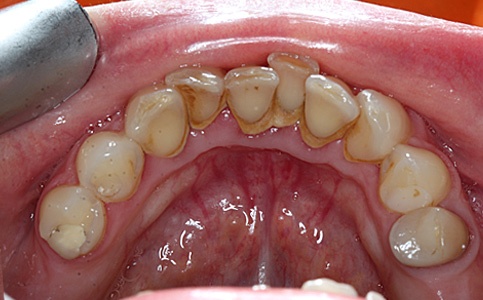

Usunięcie kamienia nazębnego.